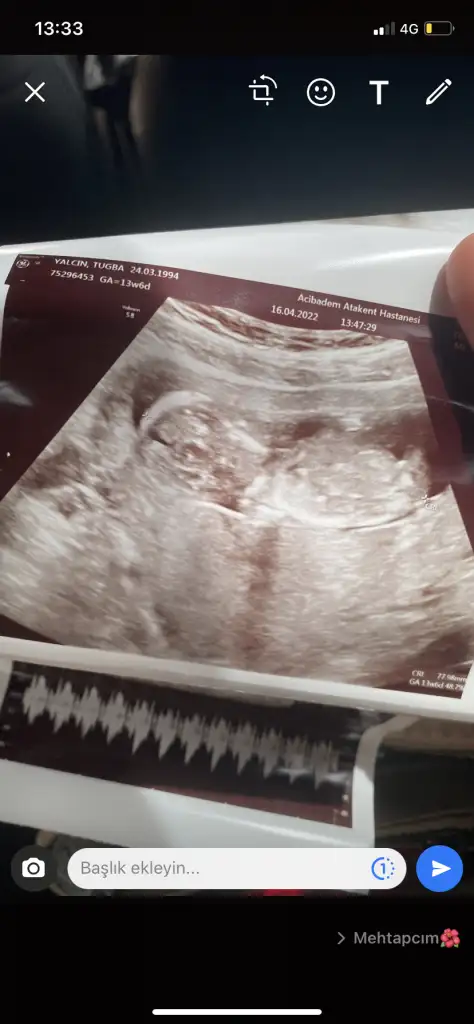

Nur ablacım doktor net söylemek için biraz daha beklemeyi tercih etti bende ısrar etmedim 1 ay sonraya kaldı😢, bu da 13+6 karından. Hala tahminin aynı mı sence merak ettim?